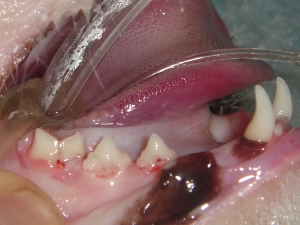

歯石除去 例2